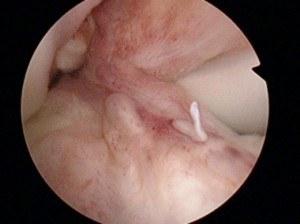

Three week old ACL Tear

Meniscus tear